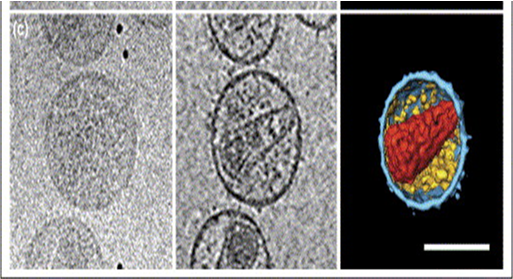

Micrografías electrónicas de partículas que muestren las dimensiones (100-120 nm) y las características morfológicas de las partículas retrovirales, y que no contengan nada más, ni siquiera partículas de otras dimensiones o morfologías.

- Las partículas supuestamente retrovirales deben tener las características morfológicas de los retrovirus:

- Los retrovirus son virus con envoltura y con un diámetro de 100 a 120 nm brotando de las membranas celulares. Los viriones liberados de las células contienen cuerpos internos condensados (núcleos), y están salpicados de protuberancias (puntas, botones). Idealmente, se tienen 72 botones en la partícula del VIH. Están hechos de gp120. En paralelo con el eje del núcleo, son visibiles acumulaciones de proteínas ("cuerpos laterales") típicas de los Lentivirinae. Morfológicamente, la naturaleza de lentivirus del VIH se refleja más claramente por el cuerpo interior alargado de forma cónica (núcleo). [Hans Gelderblom, Instituto Koch, Berlin]